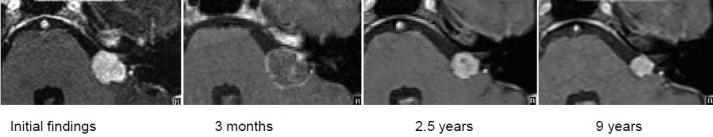

Vestibular schwannomas (VS) expand slowly in the internal auditory canal, in the cerebellopontine angle, inside the cochlear and the labyrinth. Larger tumors can displace and compress the brainstem. With an annual incidence of 1:100,000 vestibular schwannoma represent 6-7% of all intracranial tumors. In the cerebellopontine angle they are by far the most neoplasm with 90% of all lesions located in this region. Magnetic resonance imaging (MRI), audiometry, and vestibular diagnostics are the mainstays of the clinical workup for patients harboring tumors. The first part of this paper delivers an overview of tumor stages, the most common grading scales for facial nerve function and hearing as well as a short introduction to the examination of vestibular function. Upholding or improving quality of life is the central concern in counseling and treating a patient with vestibular schwannoma. Preservation of neuronal function is essential and the management options - watchful waiting, microsurgery and stereotactic radiation - should be custom-tailored to the individual situation of the patient. Continuing interdisciplinary exchange is important to monitor treatment quality and to improve treatment results. Recently, several articles and reviews have been published on the topic of vestibular schwannoma. On the occasion of the 88 annual meeting of the German Society of Oto-Rhino-Laryngology, Head and Neck surgery a special volume of the journal "HNO" will be printed. Hence this presentation has been designed to deviate from the traditional standard which commonly consists of a pure literature review. The current paper was conceptually woven around a series of interdisciplinary cases that outline examples for every stage of the disease that show characteristic results for management options to date. Systematic clinical decision pathways have been deduced from our experience and from results reported in the literature. These pathways are graphically outlined after the case presentations. Important criteria for decision making are size and growth rate of the tumor, hearing of the patient and the probability of total tumor resection with preservation of hearing and facial nerve function, age and comorbidity of the patient, best possible control of vertigo and tinnitus and last but not least the patient's preference and choice. In addition to this, the experience and the results of a given center with each treatment modality will figure in the decision making process. We will discuss findings that are reported in the literature regarding facial nerve function, hearing, vertigo, tinnitus, and headache and reflect on recent studies on their influence on the patient's quality of life. Vertigo plays an essential role in this framework since it is an independent predictor of quality of life and a patient's dependence on social welfare. Pathognomonic bilateral vestibular schwannomas that occur in patients suffering from neurofibromatosis typ-2 (NF2) differ from spontaneous unilateral tumors in their biologic behavior. Treatment of neurofibromatosis type-2 patients requires a multidisciplinary team, especially because of the multitude of separate intracranial and spinal lesions. Off-label chemotherapy with Bevacizumab can stabilize tumor size of vestibular schwannomas and even improve hearing over longer periods of time. Hearing rehabilitation in NF2 patients can be achieved with cochlear and auditory brainstem implants.

前庭神经鞘瘤(VS)在内耳道、桥小脑角、耳蜗和迷路内缓慢生长。较大的肿瘤可移位并压迫脑干。前庭神经鞘瘤的年发病率为1:100,000,占所有颅内肿瘤的6 - 7%。在桥小脑角,它们是迄今为止最常见的肿瘤,90%的病变位于该区域。磁共振成像(MRI)、听力测定和前庭诊断是患有肿瘤患者临床检查的主要手段。本文的第一部分概述了肿瘤分期、面神经功能和听力最常用的分级量表,并简要介绍了前庭功能检查。维护或改善生活质量是咨询和治疗前庭神经鞘瘤患者的核心关注点。保留神经功能至关重要,管理选择——观察等待、显微手术和立体定向放射治疗——应根据患者的个体情况量身定制。持续的跨学科交流对于监测治疗质量和改善治疗结果很重要。最近,关于前庭神经鞘瘤的主题发表了几篇文章和综述。在德国耳鼻咽喉头颈外科学会第88届年会上,将出版一期《HNO》杂志特刊。因此,本报告旨在偏离通常由纯文献综述组成的传统标准。本文围绕一系列跨学科病例进行概念性构建,这些病例概述了疾病各阶段的示例,展示了迄今为止管理选择的特征性结果。系统的临床决策路径已根据我们的经验和文献报道的结果推导得出。这些路径在病例报告后以图表形式概述。决策的重要标准包括肿瘤的大小和生长速度、患者的听力以及在保留听力和面神经功能的情况下肿瘤全切的可能性、患者的年龄和合并症、尽可能最佳地控制眩晕和耳鸣,最后但同样重要的是患者的偏好和选择。除此之外,特定中心每种治疗方式的经验和结果也将纳入决策过程。我们将讨论文献中报道的关于面神经功能、听力、眩晕、耳鸣和头痛的研究结果,并思考近期关于它们对患者生活质量影响的研究。眩晕在这个框架中起着至关重要的作用,因为它是生活质量的独立预测因素以及患者对社会福利依赖程度的指标。患有2型神经纤维瘤病(NF2)的患者出现的典型双侧前庭神经鞘瘤在生物学行为上与自发性单侧肿瘤不同。治疗NF2患者需要一个多学科团队,特别是因为存在众多单独的颅内和脊髓病变。使用贝伐单抗进行的非标签化疗可以稳定前庭神经鞘瘤的肿瘤大小,甚至在较长时间内改善听力。NF2患者的听力康复可以通过人工耳蜗和听觉脑干植入来实现。